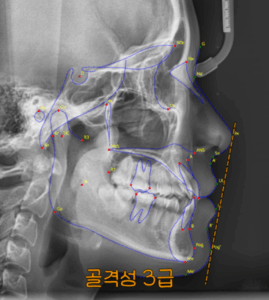

앞니 뻐드렁니 및 총생 반대교합 등 다양한 문제가 있을 때 교정치료 어떻게?

입을 열었을 때 치열이 어지럽게 놓여있다면 여러모로 신경이 쓰이게 됩니다. ​ 외적으로 안 좋은 영향을 줄 뿐만이 아닌, 기능적 측면에도 악영향을 줘서 건강을 해칠 수 있습니다. ​ 비뚤어져 있는 치열을…